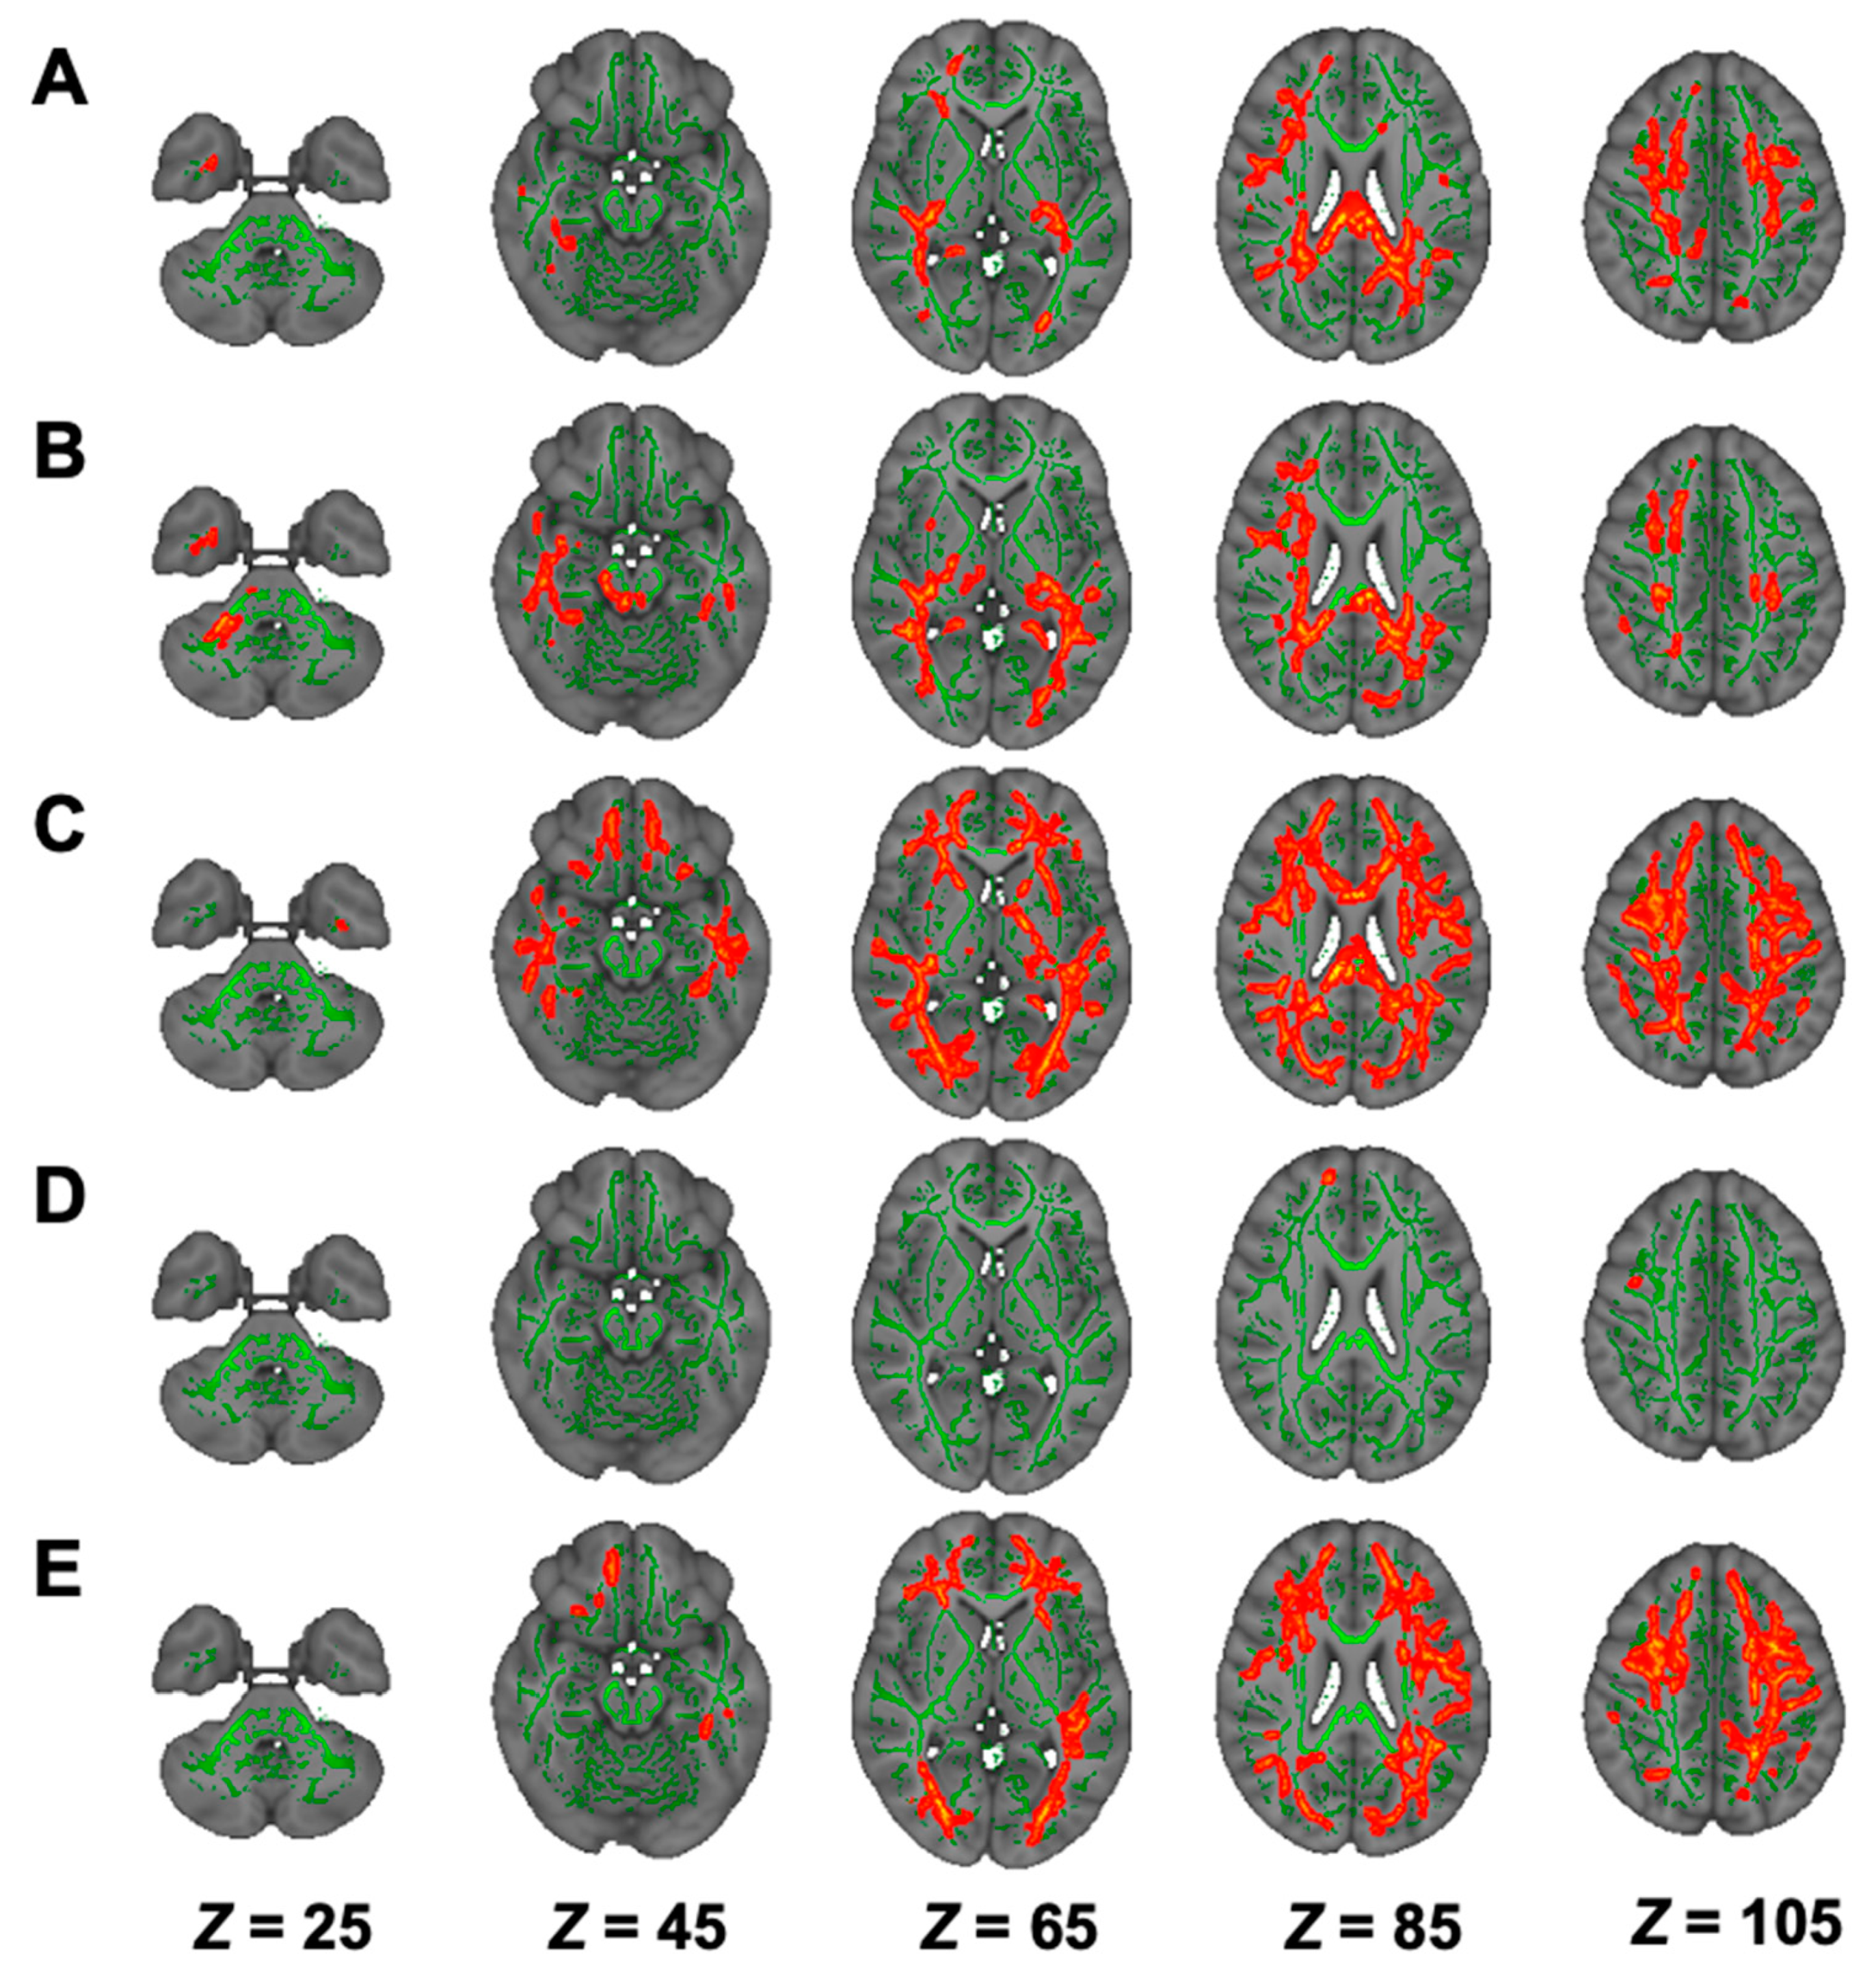

3.5. DTI Analysis in Hemodialysis Patients with NSTLC and LTLC

3.6. DKI Analysis in Hemodialysis Patients with NSTLC and LTLC

3.7. NODDI Analysis in Hemodialysis Patients with NSTLC and LTLC

| Modality | Contrast | Cluster Size | Anatomical Region | Peak t-Value | Peak MNI Coordinates (X, Y, Z) |

|---|---|---|---|---|---|

| DTI | |||||

| FA | HC > NSTLC | 48,825 | Bilateral ATR, corticospinal tract, CCG, forceps minor and major, IFOF, ILF, SLF, SLF temporal part, medial lemniscus, CP, ALIC, PLIC, retrolenticular part of IC, ACR, SCR, PCR, PTR, SS, external capsule, fornix stria terminalis, SFOF, tapetum; left UF, corticospinal tract, ICP, UF; right SCP; MCP, pontine crossing tract, genu, body and splenium of CC, fornix | 6.74 | (74, 69, 105) |

| AD | HC < NSTLC | 10,699 | Bilateral ATR, corticospinal tract, IFOF, SLF, ALIC, PLIC, retrolenticular part of IC, ACR, SCR, PCR, PTR, external capsule, fornix stria terminalis, SFOF; left ILF, SS, tapetum; forceps minor, UF, genu, body and splenium of CC, fornix | 5.85 | (50, 125, 100) |

| RD | HC < NSTLC | 49,556 | Bilateral ATR, corticospinal tract, CCG, IFOF, ILF, SLF, UF, SLF temporal part, CP, ALIC, PLIC, retrolenticular part of IC, ACR, SCR, PCR, PTR, SS, external capsule, fornix stria terminalis, SFOF, tapetum; forceps minor and major, genu, body and splenium of CC, fornix | 7.43 | (140, 117, 50) |

| MD | HC < NSTLC | 43,676 | Bilateral ATR, corticospinal tract, CCG, IFOF, ILF, SLF, UF, SLF temporal part, ALIC, PLIC, retrolenticular part of IC, ACR, SCR, PCR, PTR, SS, external capsule, fornix stria terminalis, SFOF, tapetum; left CHp; forceps minor and major, genu, body and splenium of CC, fornix | 7.10 | (53, 104, 105) |

| DKI | |||||

| AK | HC > NSTLC | 15,653 | Bilateral corticospinal tract, IFOF, ILF, SLF, PLIC, retrolenticular part of IC, ACR, SCR, PCR, PTR, external capsule, fornix stria terminalis, tapetum; right ATR, cingulum hippocampus, UF, SS, CCG, CHp; forceps minor and major, body and splenium of CC | 6.03 | (53, 65, 61) |

| HC > LTLC | 16,138 | Bilateral corticospinal tract, CHp, IFOF, ILF, SLF, SLF temporal part, corticospinal tract, medial lemniscus, SCP, CP, PLIC, retrolenticular part of IC, SCR, PCR, PTR, SS, fornix stria terminalis, tapetum; left ATR, UF, ALIC, ACR, external capsule, SFOF; forceps major, MCP, pontine crossing tract, body and splenium of CC | 6.19 | (55, 92, 82) | |

| RK | HC > NSTLC | 45,239 | Bilateral ATR, corticospinal tract, CCG, IFOF, ILF, SLF, UF, SLF temporal part, ALIC, retrolenticular part of IC, ACR, SCR, PCR, PTR, SS, external capsule, fornix stria terminalis, SFOF; right UF, tapetum; forceps minor and major, genu, body and splenium of CC | 6.11 | (98, 172, 110) |

| HC > LTLC | 69 | forceps minor | 4.89 | (79, 177, 101) | |

| MK | HC > NSTLC | 28,546 | Bilateral ATR, IFOF, ILF, SLF, ALIC, ACR, SCR, PCR, PTR, SS, external capsule, SFOF; left corticospinal tract, UF, retrolenticular part of IC; forceps minor and major, genu, body and splenium of CC | 6.82 | (97, 141, 131) |

| NODDI | |||||

| ICVF | HC > NSTLC | 67,959 | Bilateral ATR, corticospinal tract, CCG, IFOF, ILF, SLF, UF, SLF temporal part, CP, ALIC, PLIC, retrolenticular part of IC, ACR, SCR, PCR, PTR, SS, external capsule, CHp, fornix stria terminalis, SFOF, tapetum; left UF; right CHp; forceps minor and major, genu, body and splenium of CC | 8.15 | (106, 82, 84) |

| HC > LTLC | 38,021 | Bilateral ATR, corticospinal tract, CCG, IFOF, ILF, SLF, UF, SLF temporal part, ALIC, PLIC, retrolenticular part of IC, ACR, SCR, PCR, PTR, SS, external capsule, CHp, fornix stria terminalis, SFOF; left tapetum; right CHp, CP; forceps minor and major, genu, body and splenium of CC | 6.22 | (113, 63, 103) | |

| ISO | HC > LTLC | 3978 | right ATR, Inferior fronto-occipital fasciculus, ILF, UF, retrolenticular part of IC, ACR, SCR, PTR, SS; forceps minor and major | 5.88 | (48, 116, 49) |

| NSTLC > LTLC | 8312 | Bilateral corticospinal tract, IFOF, ILF, SLF, UF, SCP, CP, retrolenticular part of IC, PTR, SS; right ATR, CHp, SLF temporal part, ALIC, PLIC, external capsule, fornix stria terminalis; forceps minor and major, MCP, pontine crossing tract | 7.52 | (129, 83, 68) | |